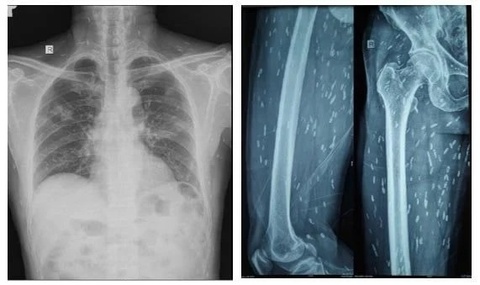

Ấu trùng sán dải lợn có hình thái như hạt gạo hoạt động “ẩn nấp” chi chít ở phổi và vôi hóa trong mô da, cơ trên toàn bộ cơ thể người bệnh - Ảnh: Bệnh viện cung cấp

Sau đó, bệnh nhân được chụp X-quang xương đùi, CT-scan ngực để tầm soát tổn thương thì phát hiện vô số nang sán dải lợn còn sống, hoặc đã bị hóa vôi trong não, nhu mô phổi, và trong da, cơ trên toàn bộ cơ thể người bệnh.

Bệnh nhân được chẩn đoán viêm não do nang sán dải lợn và nhiễm nang sán dải ở đa cơ quan, nổi bật nhất là ở não, mô dưới da và ở cơ.